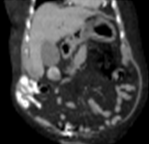

Contrast-enhanced CT of the abdomen, revealing air in intrahepatic biliary tree (pneumobilia) (red arrow)